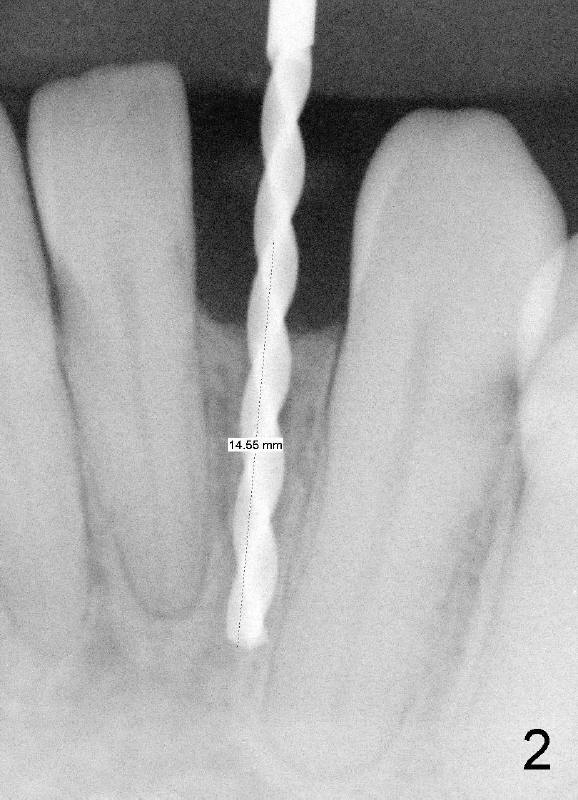

A 44-year-old black lady with ortho several years ago requests fixed restoration for #23 with narrow mesiodistal width (Fig.1). Treatment options are proposed: fixed prosthetic denture and implant. After discussion of advantages and disadvantages of each option, the patient agrees to have implant restoration. A 1.5 mm pilot drill is used to create osteotomy (Fig.2,3). After using 2.0 mm and 3.0 mm tapered osteotomes through the cortex at the crest, 3x17 mm 1-piece implant is placed (Fig.4) and temporary crown is immediately cemented with no centric or lateral occlusion. The patient is doing fine postop, although there is very mild percussion involving the tooth #24, three days postop. Fig.5 and 6 show that the temporary crown is bonded to the neighboring teeth interproximally and lingually. Retrospectively, ortho should have been done to torque the root of the tooth #22 prior to implant placement. Fig.3,4 show that there is space between #21 and 22.